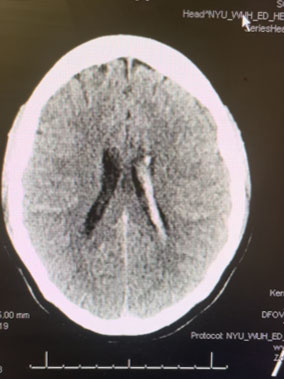

Imaging:

Head CT was consistent with a small acute left intraventricular hemorrhage (Figure 1).

Fig. 1